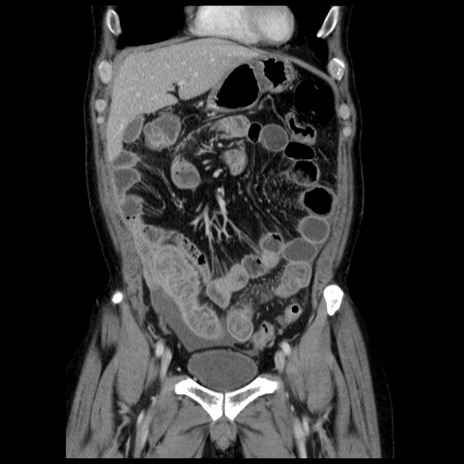

症例29(冠状断像)

【症例】40歳代男性

【現病歴】2日前から胃痛あり。徐々に周期的な激痛に変化した。本日になっても激痛があるため受診。

【身体所見】意識清明、BT 38-39℃台あり、腹部:膨満、やや硬、右下腹部に圧痛あり。

【データ】WBC 8500、CRP 23.26